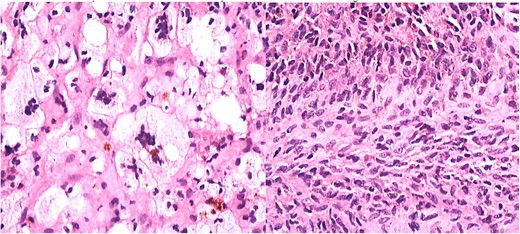

During the arthroscopic procedure, extensive synovial proliferation and a well-defined mass were identified within the joint space. The mass was excised, and the synovium was sampled for histopathological evaluation (Fig. 2). The pathology report confirmed the diagnosis of an SGCT, a rare entity within the hip joint (Fig. 3).

Histopathology showing proliferation of mononuclear synovial cells with oval or polygonal shapes and multinucleated giant cells resembling osteoclasts.

The histopathological examination revealed a nodular proliferation of mononuclear and multinucleated giant cells, consistent with an SGCT. These tumors typically exhibit mild to moderate cellular atypia without significant mitotic activity, which contributes to their localized and aggressive nature. The tumor’s rare occurrence in synovial tissue underscores its complexity and the need for precise diagnostic methods [3].